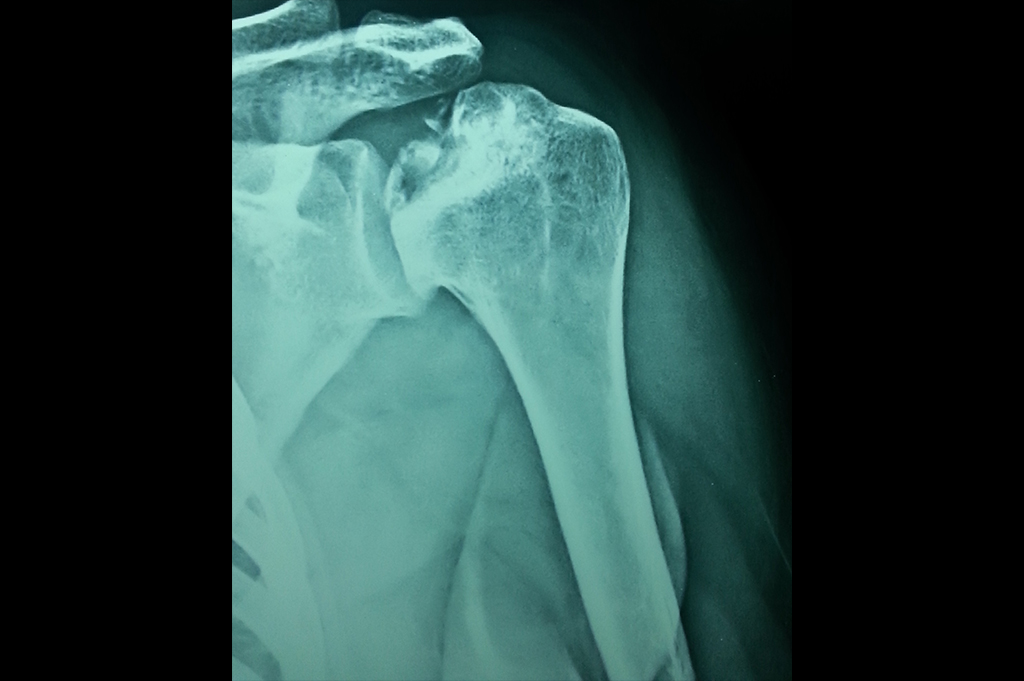

Proximal Humerus